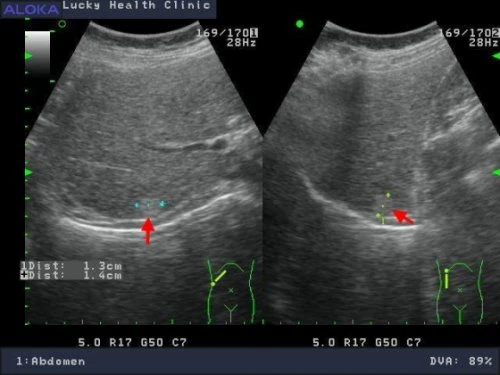

正常肝臟![]() Rt liv :右葉肝臟 IVC :下腔靜脈 hepatic V :肝靜脈 ![]() Lt liv :左葉肝臟 , LHV :左側肝靜脈 , LPV :左側肝門靜脈 , IVC :下腔靜脈 , SMA :上腸繫膜動脈 , SV :脾靜脈 , P :胰臟 , AORTA:主動脈 肝癌 ![]() 肝硬化合併早期肝癌1.4公分 ![]() 轉移性肝癌 ![]() 肝癌局部復發 1.6 公分 ![]()